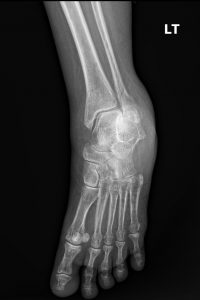

Fig. 1 Posterior view of the foot

Standard plain film radiography is the cornerstone of diagnosis for a suspected lateral malleolar fracture. A proper ankle series must include at least three views to fully assess the bone and joint integrity:

1. Anteroposterior (AP) View: A straight-on view from the front. It is useful for assessing the general alignment of the tibia and fibula.

3. Mortise View: This is the most critical view for assessing the stability of the ankle joint. It is taken like an AP view but with the leg internally rotated by 15-20 degrees. This rotation brings the lateral and medial malleoli into the same plane, providing a true, unobstructed view of the entire ankle mortise.